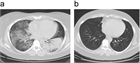

1. 初期治療のステロイドは1 mg/kgで開始する。腎機能が保たれている比較的軽症の場合、ステロイドは0.5 mg/kgで開始できる可能性がある。急速進行性糸球体腎炎や広範な肺病変を伴う場合は、導入時にステロイドパルス併用が推奨される。シクロホスファミドやリツキシマブの併用が推奨される(推奨度1)